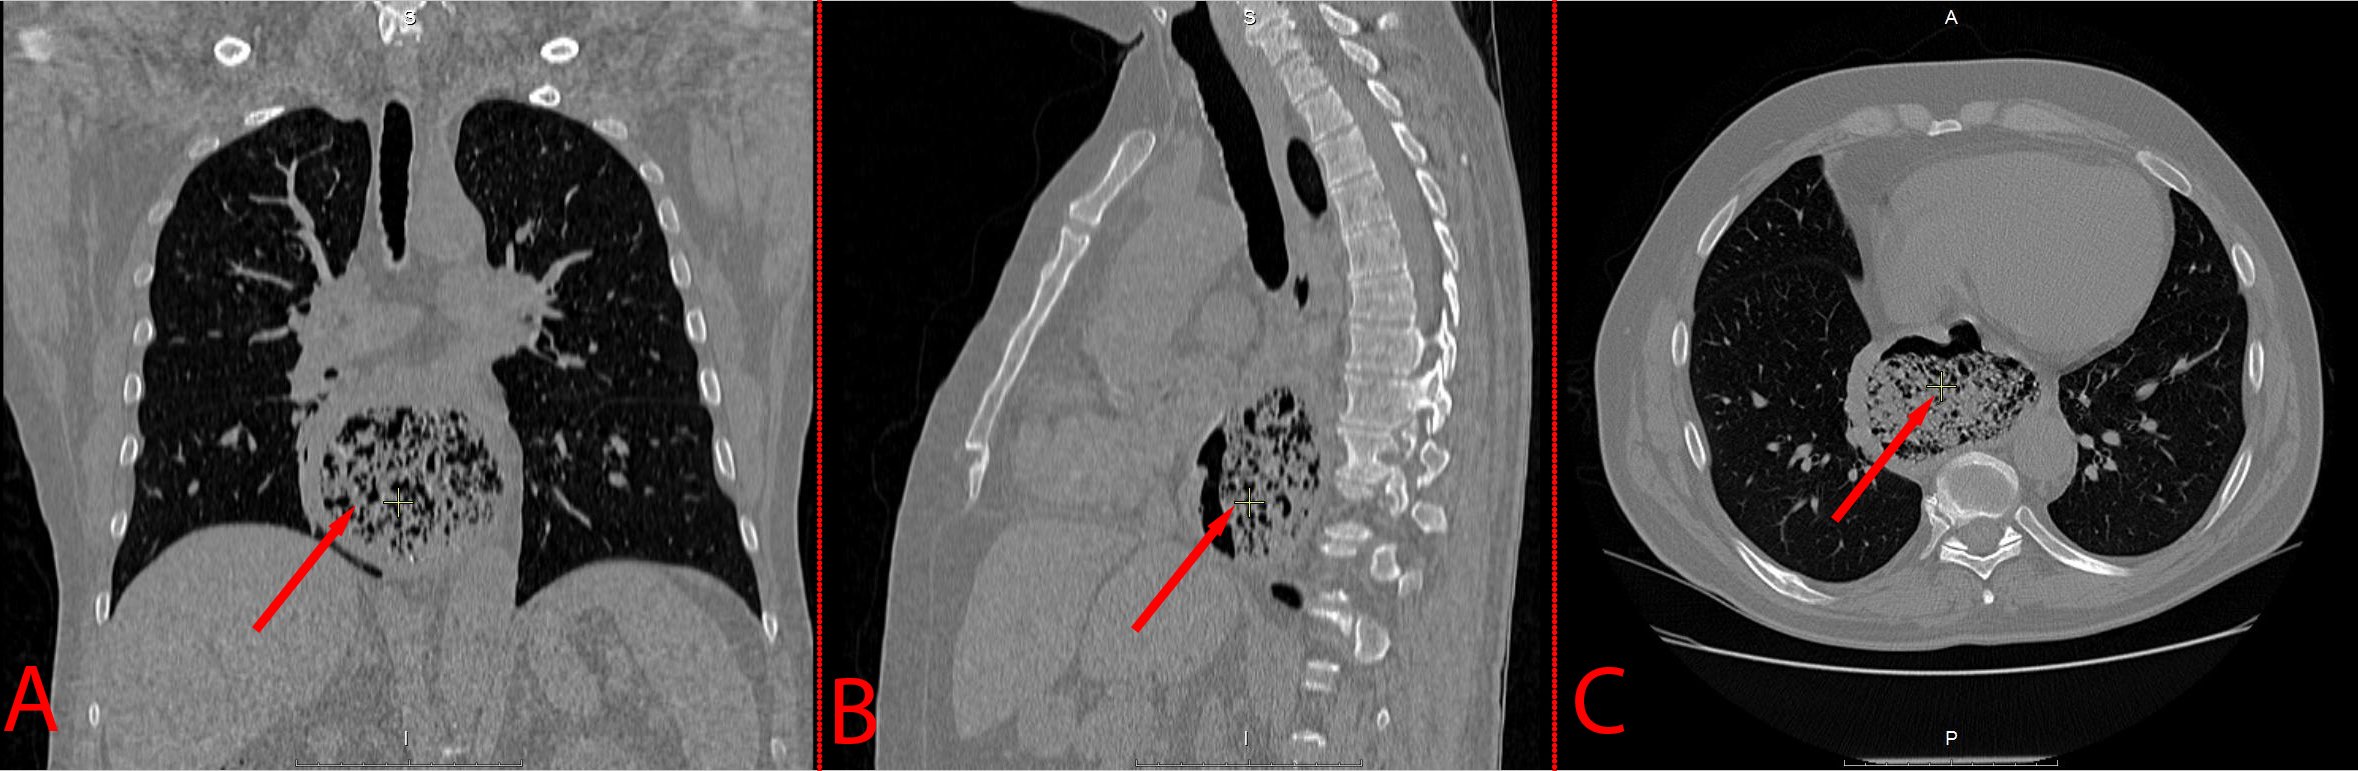

A 54-year-old man was admitted to the hospital with complaints of pain in xiphoid region after eating, dysphagia and bad breath. The symptoms persisted for the last 3 months. During the inspection, no visible changes were found. The patient had several comorbidities: grade II hypertension, grade 3 cardiovascular risk; and stage 1 chronic obstructive pulmonary disease, type A GOLD (Global Initiative for Chronic Obstructive Pulmonary Disease). Body mass index - 22.53, blood pressure - 150/90 mm Hg. Computer tomography (CT) of the chest cavity revealed a protrusion of the esophagus wall anteriorly up to 80x90 mm in diameter, with a vertical size of 60 mm, located at the border of the middle and lower third of the esophagus, 20 mm below the tracheal bifurcation. The size of the diverticulum was 88x60x90 mm, with the presence of heterogeneous contents in the cavity (Figure 1). The lungs were emphysematous, with a few thin-walled air cavities in both apexes. Based on the data obtained, the patient was diagnosed with an epiphrenic diverticulum. Considering the size of the diverticulum, as well as the presence of symptoms, the patient had indications for surgery.

A: Coronal plane; B: Sagittal plane; C: Axial plane (arrow points at the diverticular sac).